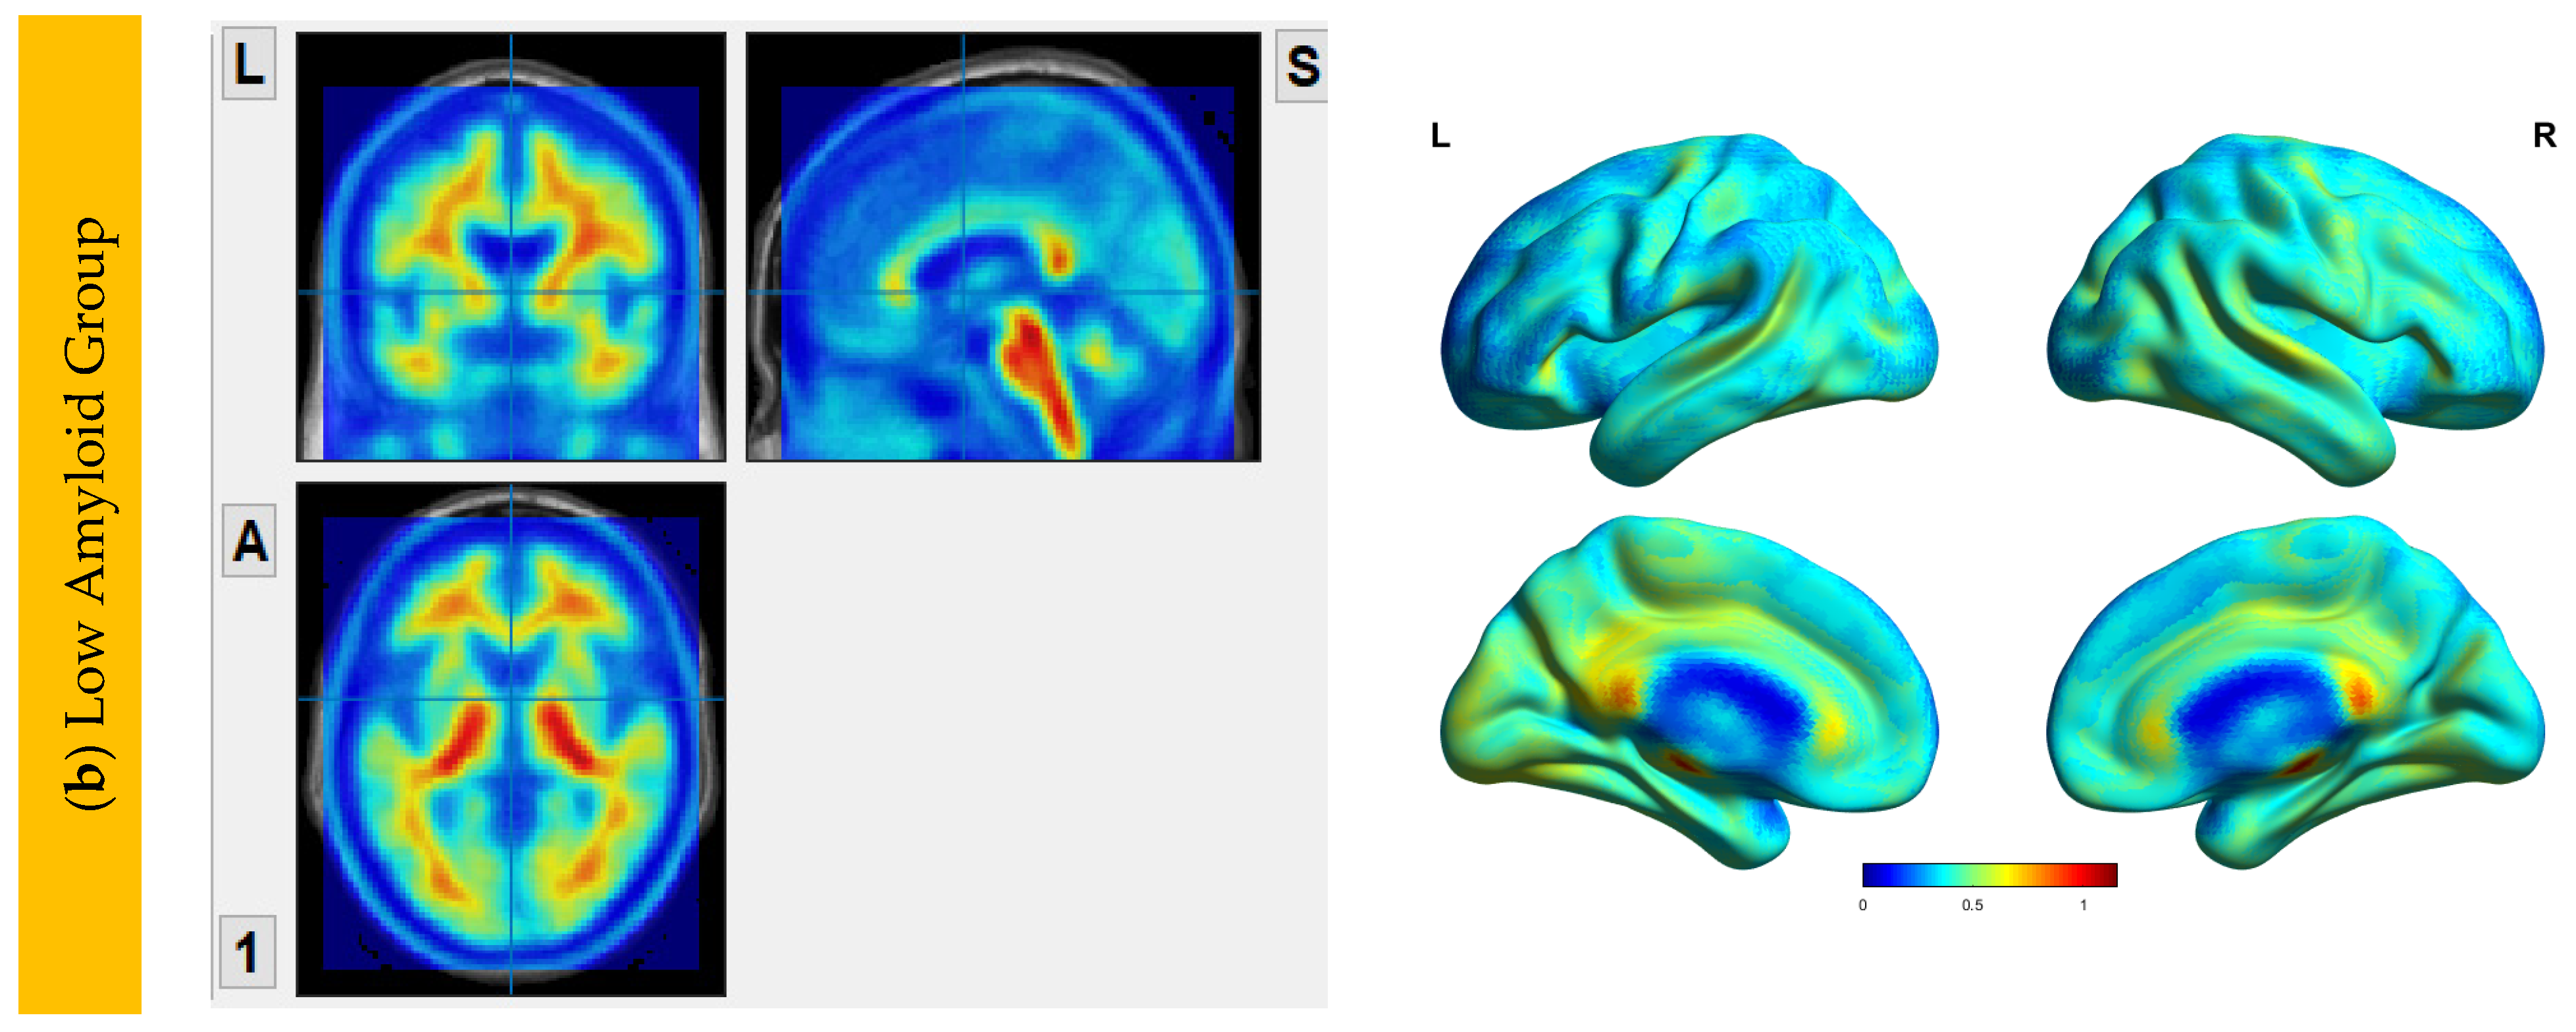

6.2. Aβ Protein Accumulation (SUVr) Maps

6.3. Interhemispheric Functional Connectivity (VMHC) Maps